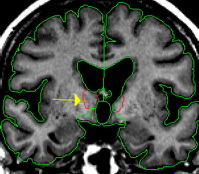

Use the intensity contour function to obtain an outline that tightly hugs the lateral edge of the thalamus but does not exclude any thalamus. This contour will provide most or all of the lateral border of the thalamus and should meet the superior border provided by the caudate or lateral ventricle. Some manual drawing may be necessary, particularly along the ventro-lateral border. This border should never extend to the pallidum. Projection lines should be used in conjunction with sagittal and axial views when boundaries become less clear.

The dorsal medial border must be drawn in in order to exclude the fornix and separate the thalamus from the tissue between the ventricles. This is achieved by manually drawing in the border along the foramen of monroe or, if the foramen of monroe is not visible, from the bottom corner of the lateral ventricle to the medial cerebral exterior line or third ventricle.